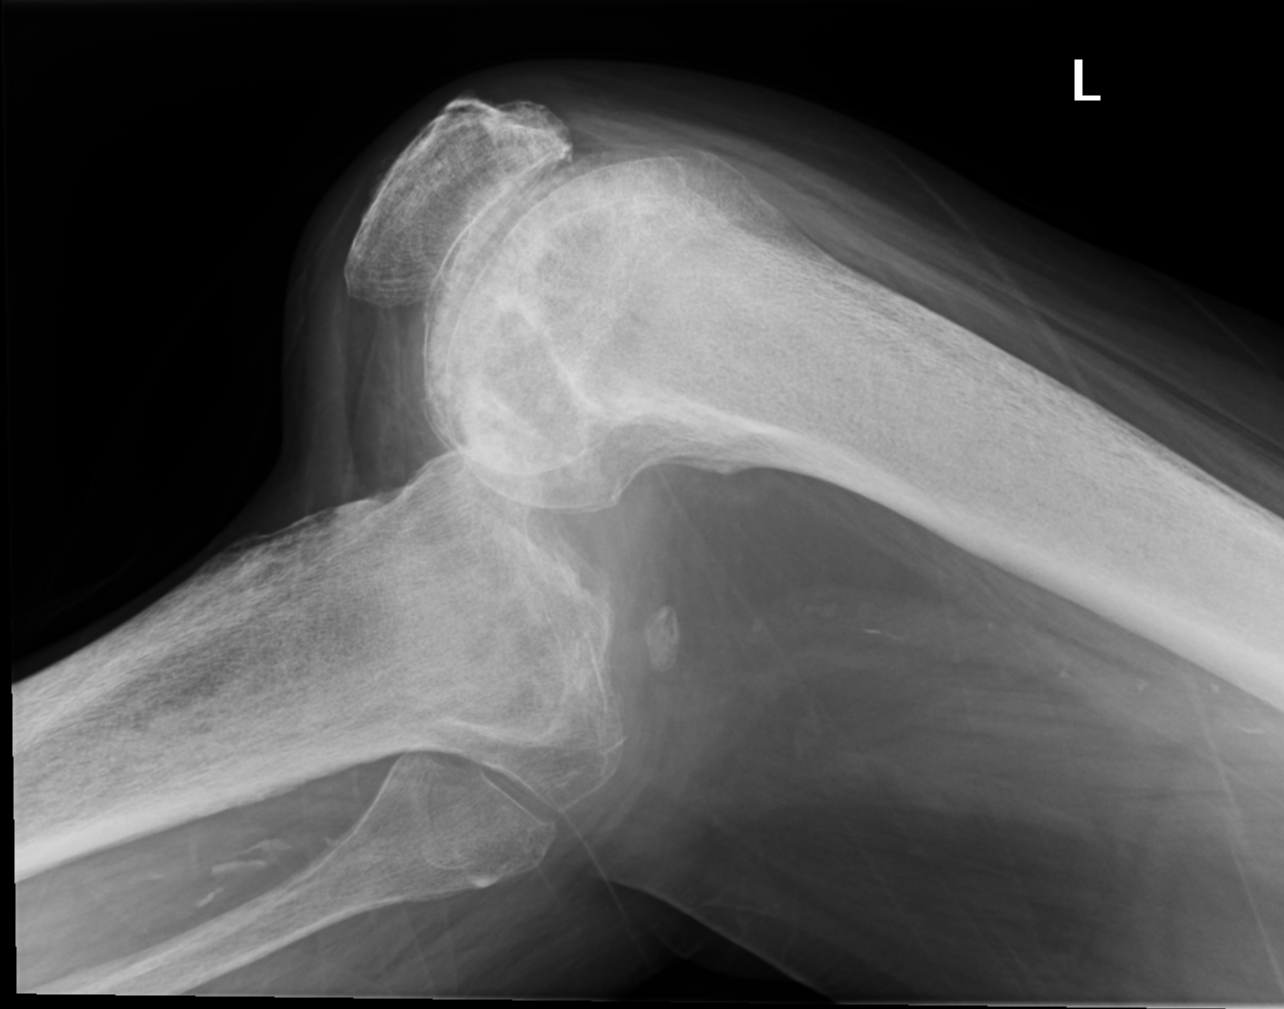

Luxation de genou

Daniel J Bell,

Radiopaedia.org

. From the case

rID: 96268

Avis chirurgical en urgence,

risque vasculaire ++

(artère poplitée).